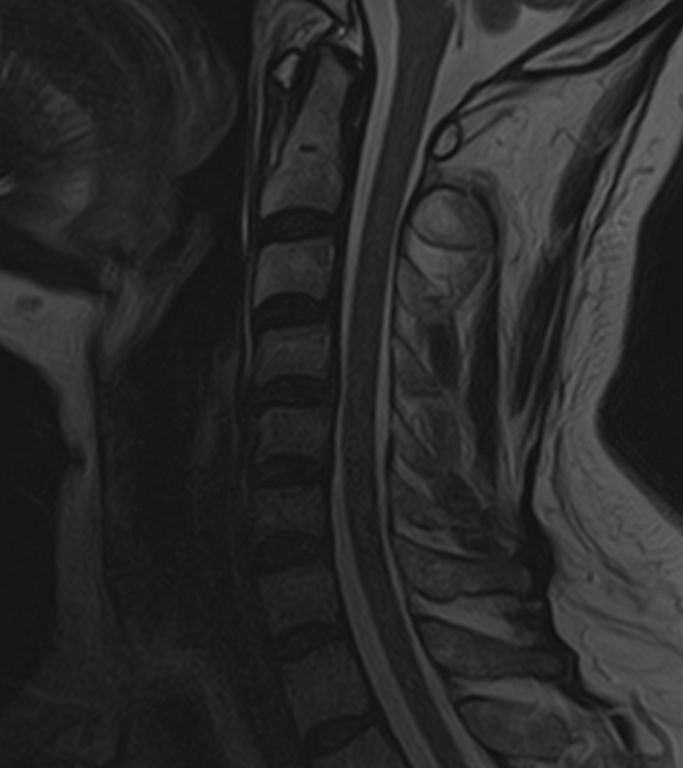

Для диагностики заболеваний ЦНС в клинике «Доступная медицина» проводится комплексное обследование МРТ ЦНС (центральной нервной системы). Клиника укомплектована высокотехнологичным оборудованием, в частности, новейшим 32-канальным высокопольным томографом TOSHIBA VANTAGE TITAN 1,5 Тесла с высокой разрешающей способностью для точной диагностики заболеваний центральной нервной системы.

МРТ центральной нервной системы (ЦНС) (головной мозг + 3 отдела позвоночника)

13 400 / 12 200 руб

Подробнее